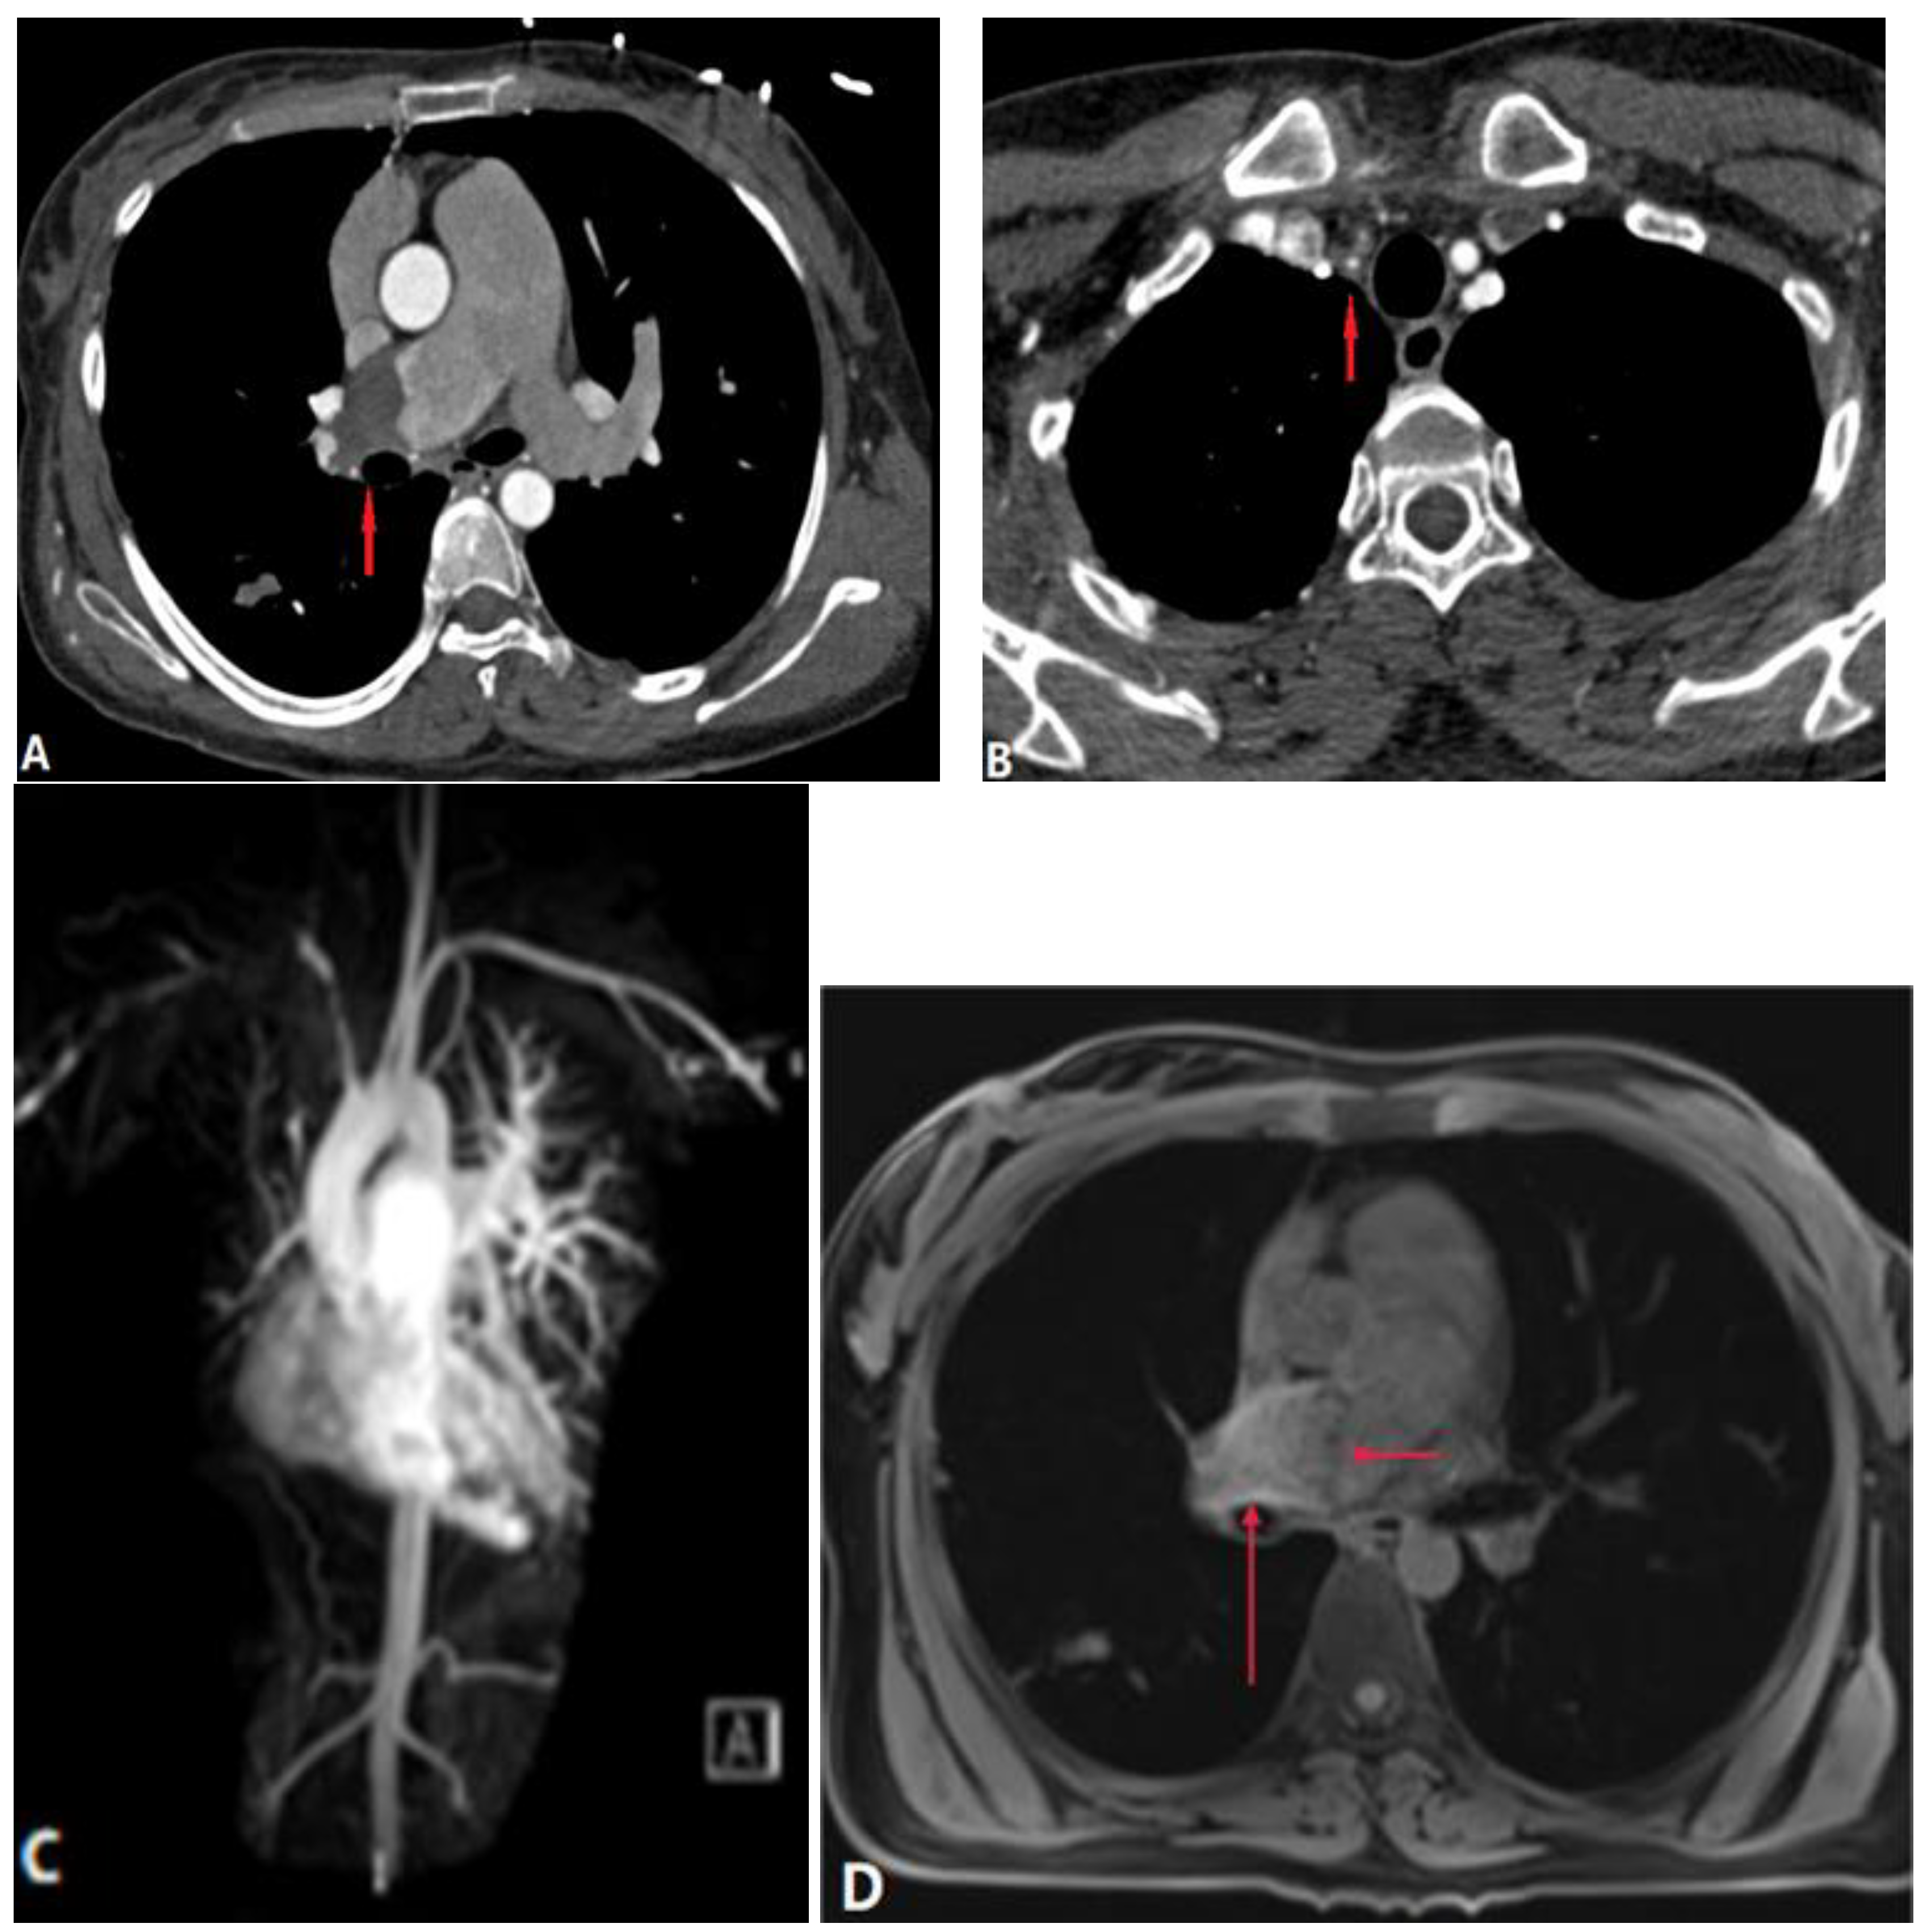

4.2.4. Arterial Dissection (AD)

4.3. Extra-Luminal Abnormalities

5. Complications of Radiofrequency Ablation of Atrial Fibrillation